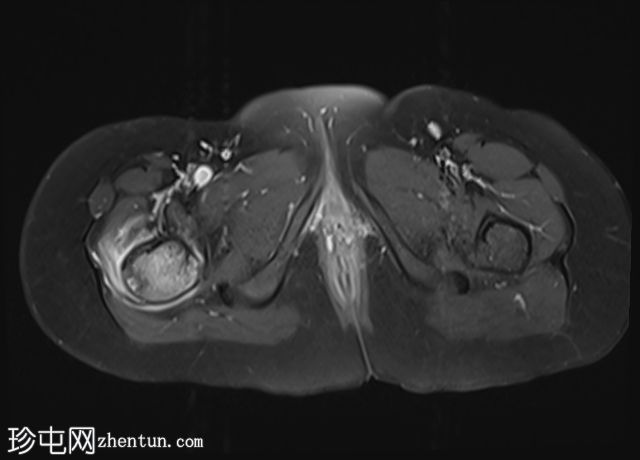

髋部

MRI

冠状位

T1

轴向

轴向PD

脂肪饱和度

轴向T1

C+脂肪饱和度

右上股骨大转子正下方外侧皮质区可见一小的皮质基部病变,边缘呈低信号,大小约为0.7 x 0.7厘米。

邻近的股骨近端骨干和股骨颈有水肿。

水肿有扩散至邻近肌肉的迹象。